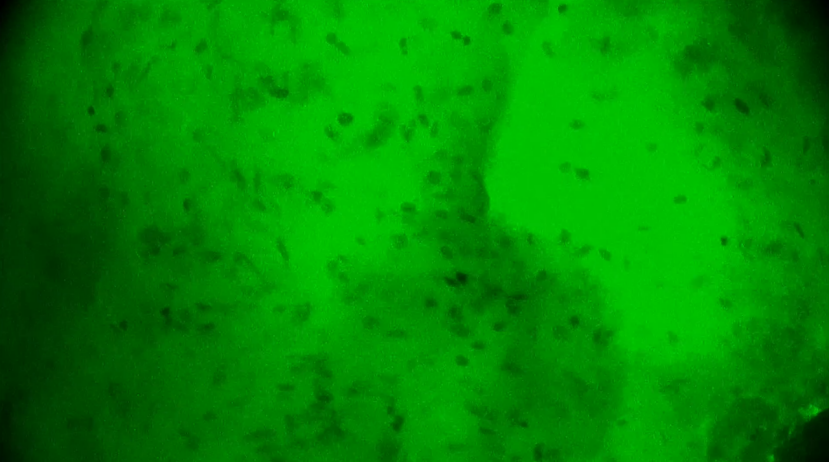

第3次掃查瘤腔,細(xì)胞核分布規(guī)則,無異型性,陰性。